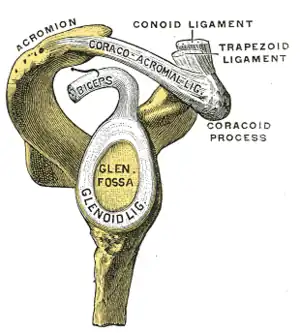

Le chef court du muscle biceps brachial se fixe sur la partie latérale de l'apex du processus coracoïde de la scapula par un tendon commun avec le muscle coraco-brachial.

L'origine du chef long du muscle biceps brachial est intra-capsulaire de l'articulation gléno-humérale et se fixe sur le tubercule supraglénoïdal de la scapula[1] ainsi que sur la partie haute du labrum glénoïdal de la scapula.

SLAP est l'acronyme de Superior Labrum from Anterior to Posterior. La SLAP lesion est un arrachement du bourrelet glénoïdien supérieur. Elle se produit le plus souvent lors des mouvements de traction dans les sports de lancer (Baseball)[4],[5].

Origines scapulaires des deux chefs du muscle biceps brachial.

Origines scapulaires des deux chefs du muscle biceps brachial. Origine du chef long du muscle biceps brachial